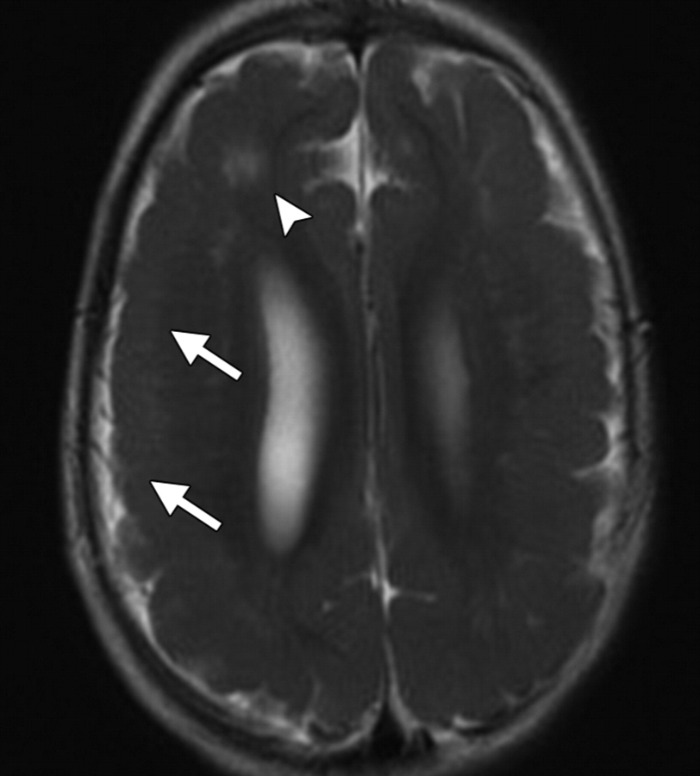

(а) Бесконтрастная КТ, аксиальный срез: у молодого взрослого с изменениями психического состояния в левой височной доле определяется отек и геморрагический компонент. Несмотря на раннее начало лечения ацикловиром данный пациент погиб. Смертность среди пациентов с герпетическим энцефалитом (ГЭ) варьирует от 50 до 70%.

(б) МРТ, Т1-ВИ, сагиттальный срез: у пациента через две недели после развития клинической картины герпетического энцефалита определяется потеря объема мозговой ткани височной доли. Кроме того, визуализируются линейные повторяющие ход извилин участки повышения интенсивности сигнала, которые расположены в структуре коры височной доли и характерные для подострого кортикального кровоизлияния.